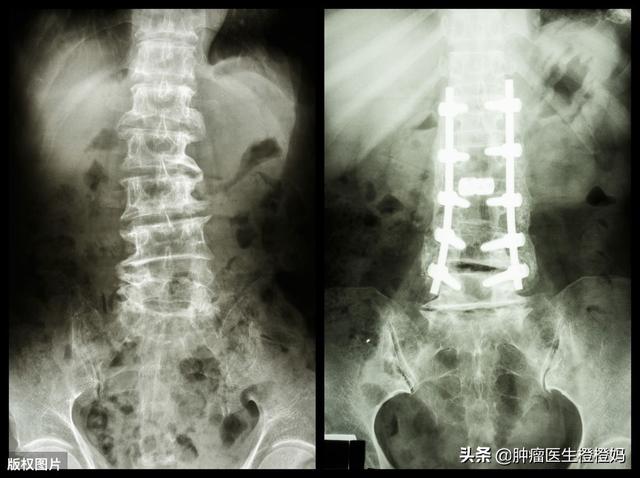

- 骨折があれば、整形外科医の助けを借りなければなりません。状況によっては、大腿骨固定や椎体セメント充填などをしなければならないかもしれません。そして怪我を悪化させないためには、骨折部位の動きを避けることが重要である。

骨転移は一般に直接生命を脅かすものではなく、予後もがんによって大きく異なるが、椎体や大腿骨など荷重のかかる骨に発生した骨転移は潜在的に危険であり、例えば椎体骨折で半身不随になることは非常に厄介である。したがって、骨転移が発見されたら、骨破壊を抑制し、患者のQOLを改善するために積極的な介入が必要である。